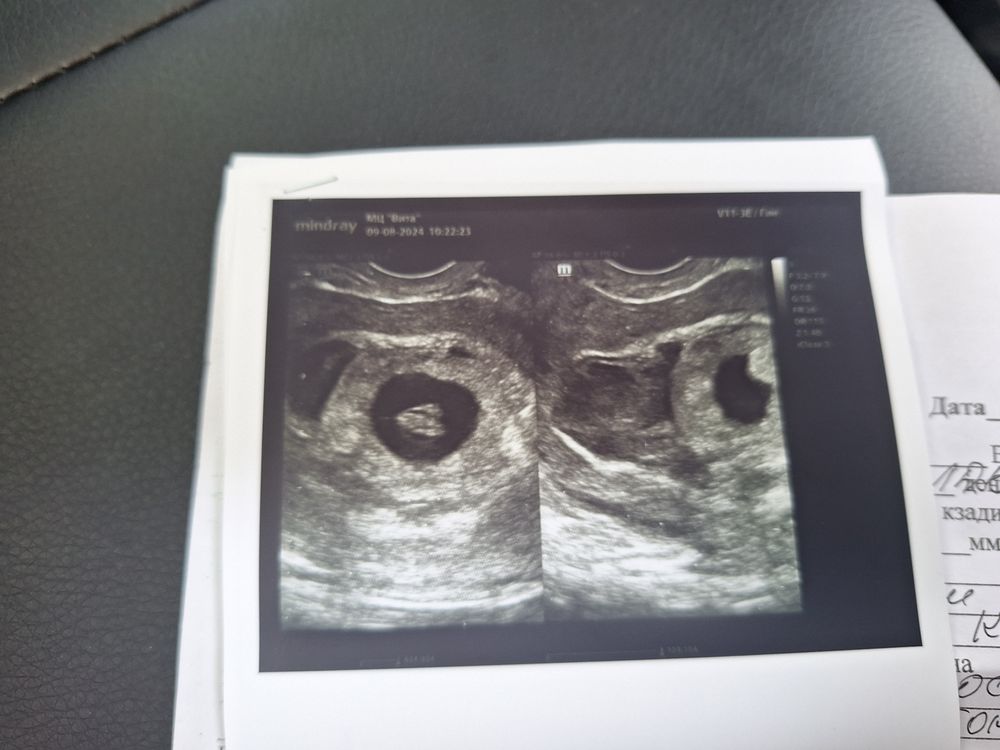

Мы 11 мм. СБ 155

Мы развиваемся! Гемотома большая!